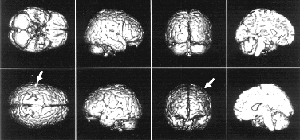

| Интересные результаты даёт такой эксперимент. Испытуемому рассказывают одновременно две разные истории: в левое ухо одну, в правое — другую. На верхнем фото изображены разные проекции мозга — стрелками отмечены активизированные зоны, когда внимание сосредоточено на истории, рассказываемой в левое ухо. Внимание испытуемого „переключилось“ на „историю в правом ухе“ (нижнее фото). Можно заметить, что для фиксации внимания на „историю в правом ухе“ требуется гораздо меньшая активность мозга. Это связано с праворукостью большинства людей — обычно они берут телефонную трубку правой рукой и прикладывают её к правому уху. |

Кроме непроизвольного внимания есть ещё и селективное. Это так называемое „внимание на приёме“, когда все вокруг говорят разом, а вы следите только за собеседником, не обращая внимания на неинтересную вам болтовню соседа справа. Во время эксперимента испытуемому рассказывают истории: в одно ухо — одну, в другое — другую. Мы следим за реакцией на историю то в правом ухе, то в левом и видим на экране, как радикально меняется активизация областей мозга. При этом активизация нервных клеток на историю в правом ухе значительно меньше — потому, что большинство людей берут телефонную трубку в правую руку и прикладывают её к правому уху. Им следить за историей в правом ухе проще, нужно меньше напрягаться, мозг возбуждается меньше.